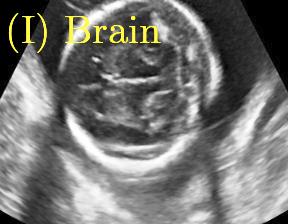

Row I in Fig. 6 shows a fetal brain image from . The confidence estimation of shadow regions from the baseline, the proposed method and the proposedAG method are similarly accurate since we use fetal brain images to train the confidence estimation networks in these three methods. These outperform [16] and [22]. Rows (II-IV) in Fig. 6 show shadow confidence maps of non-brain anatomy from , including lips, abdominal and cardiac. The baseline failed on unseen data during inference. However, the proposed methods are able to generate accurate shadow confidence maps because of the generalized shadow features obtained by the shadow-seg module. Furthermore, the “Lips” example shows that our method is capable of detecting weaker shadow regions that have not been annotated in manual segmentation. This indicates that the confidence estimation network has learned general properties of shadow regions.

We propose a novel method based on convolutional neural networks (CNNs) to automatically estimate pixel-wise confidence maps of acoustic shadows in 2D US images. Our method learns an initial latent space of shadow regions from images consisting of multiple anatomies and with global image-level labels (“has shadow” and “shadow-free”), e.g. Fig. 1(a). The basic latent space is then estimated by learning from fewer images of a single anatomy (fetal brain) with coarse pixel-wise shadow annotations (approximately of the images with global image-level labels), e.g. Fig. 1(b). The resulting latent space is then refined by learning shadow intensity distributions using fetal brain images so that the latent space is suitable for confidence estimation of shadow regions. By using shadow intensity information, our method can detect more shadow regions than the coarse manual segmentation, especially relatively weak shadow regions.